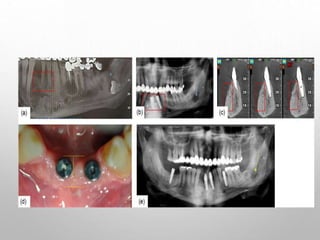

ROLE OF CBCT IN DIAGNOSIS

CBCT is required in the preoperative assessment of IMTM when darkening of

the roots and interruption of the white line are observed on panoramic images.